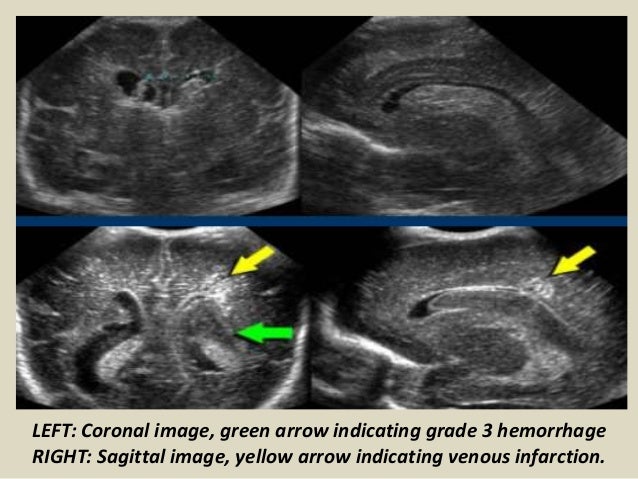

18. 18. LEFT: Coronal image, green arrow indicating grade 3 hemorrhage RIGHT: Sagittal image, yellow arrow indicating venous infarction.

19. 19. Sagittal section - grade III - GMH and IVH with ventricular dilation (white arrows).

20. 20. Intracranial hemorrhage grade 4